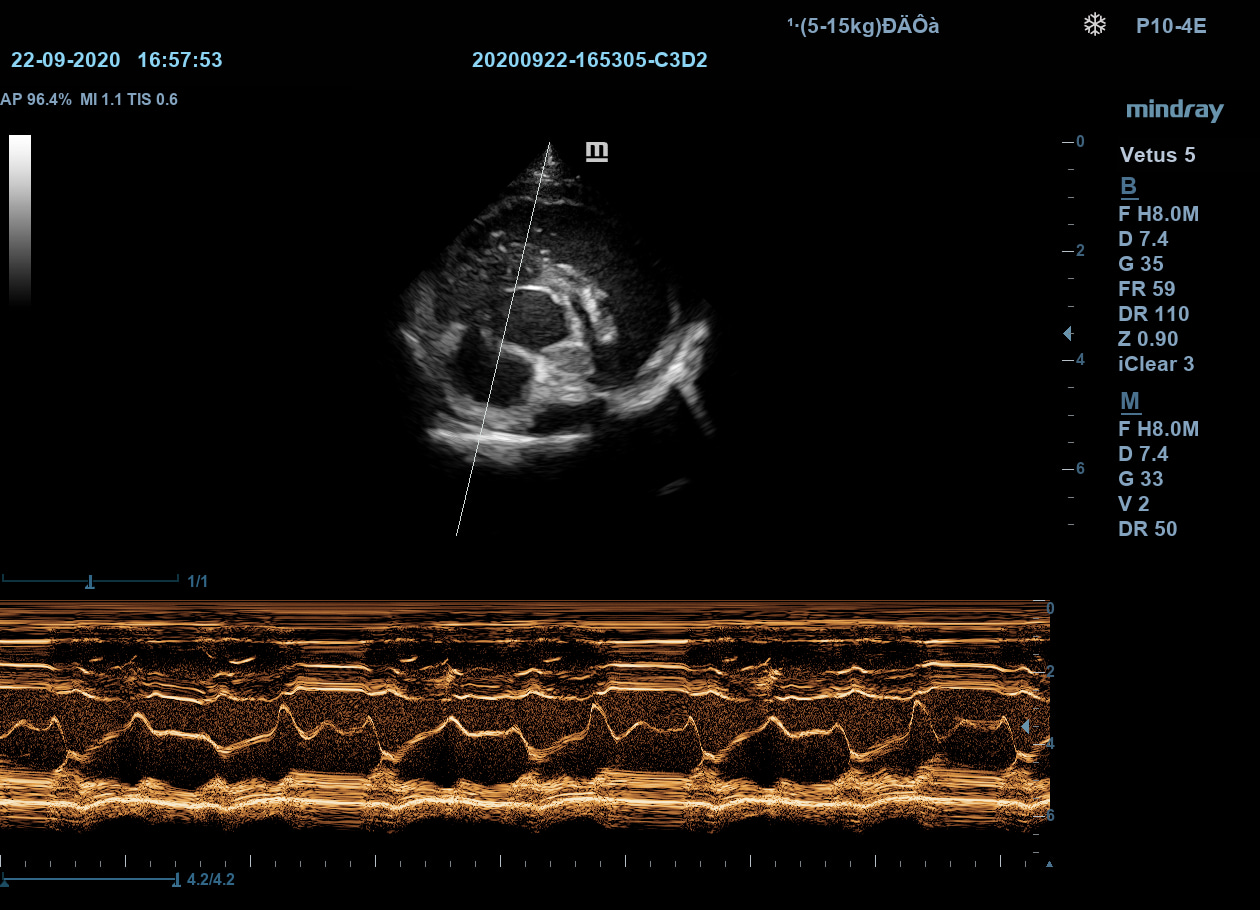

Free Xros M – анатомический М-режим

При наличии записанной в память прибора видео петли, режим позволяет провести линию М-режима в любом месте, при этом корректируя изначально не оптимальный угол.

Free Xros M – анатомический М-режим

При наличии записанной в память прибора видео петли, режим позволяет провести линию М-режима в любом месте, при этом корректируя изначально не оптимальный угол.